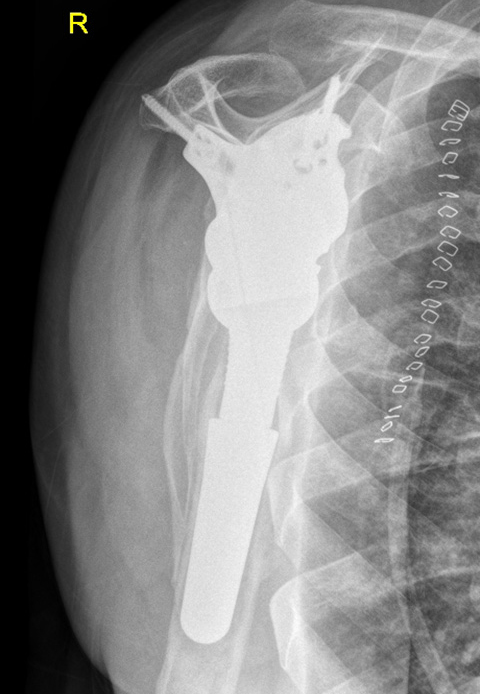

Post-op

Implants used:

- customLINK implant was a perfect fit

- Stable fixation of glenoid with seven bone screws

- Eccentric Glenosphere 42 mm / 4mm

- Modular Revision Stem, 75 mm length, size 24 mm

- Proximal Body, size L, height +5 mm

- Reverse Humeral Tray, neutral

- Reverse Humeral Insert, UHMWPE, dia. 42 mm, height 6 mm, 10° inclined

Final result:

- Good range of motion

- Good joint stability

- Good pain relief